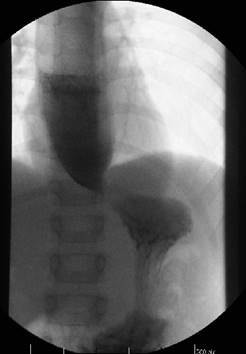

El tratamiento definitivo fue quirúrgico mediante miotomía de Heller con funduplicatura anterior de Dorr por abordaje convencional, sin incidentes. Presentó buena evolución clínica, con tolerancia de alimentos líquidos y sólidos. Luego del tratamiento quirúrgico se realizó un nuevo estudio radiológico baritado que mostró pasaje de contenido esofágico al estómago (Figura 3).